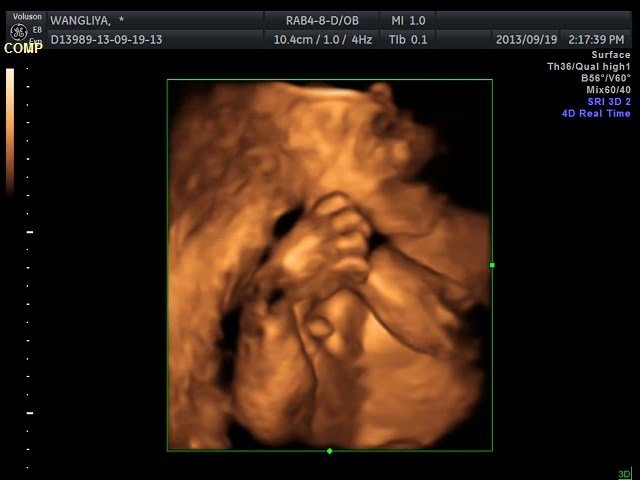

什么四维彩超我根本就看不懂,有谁能帮我看看? 点击展开 匿名用户 2013-09-22 08:47 为您推荐: 其他回答 你这是四维的截图阿,医生看的那种,如果是做四维会给你出四维报告单的,上面有具体的项目数据。你这个除了专业医生谁也看不懂。 穰嘉言_GXLL 2013-09-29 18:33 彩超不是下面有文字说明的吗 捷飞掣_73mU 2013-09-24 13:58 在做四维的时候,医生都会在旁边进行解答的呀,你怎么会看不懂呢 务涵育_6fMR 2013-09-22 10:02 相关问题 今天刚做的四维彩超,自己看不懂,麻烦帮我看看有没有什么问题? 四维彩超已做,来帮我看看!是男宝 拜托有经验的帮我看看,现在能看到是男是女吗?还有宝宝有什么不好吗?看不懂这个b超单啊!